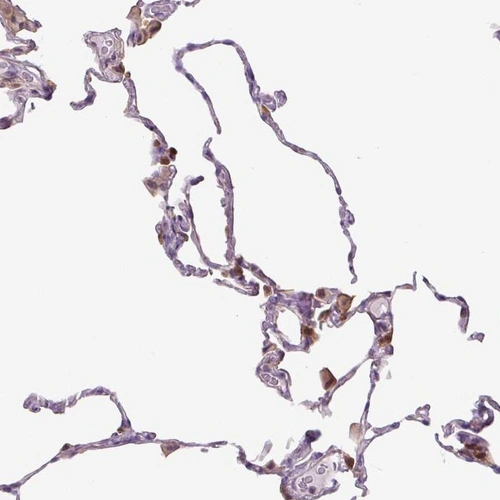

Immunohistochemical staining of human lung shows moderate cytoplasmic positivity in macrophages.